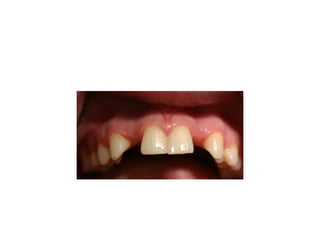

Management of missing upp incisor

• Upper central incisors are rarely congenitally

absent. They can be lost as a result of trauma,

or occasionally their extraction may be

indicated because of dilaceration. Upper

lateral incisors are congenitally absent in

approximately 2 per cent of a Caucasian

population, but can also be lost following

trauma. Both can occur unilaterally, bilaterally,

or together. Whatever the reason for their

absence. there are two treatment options: